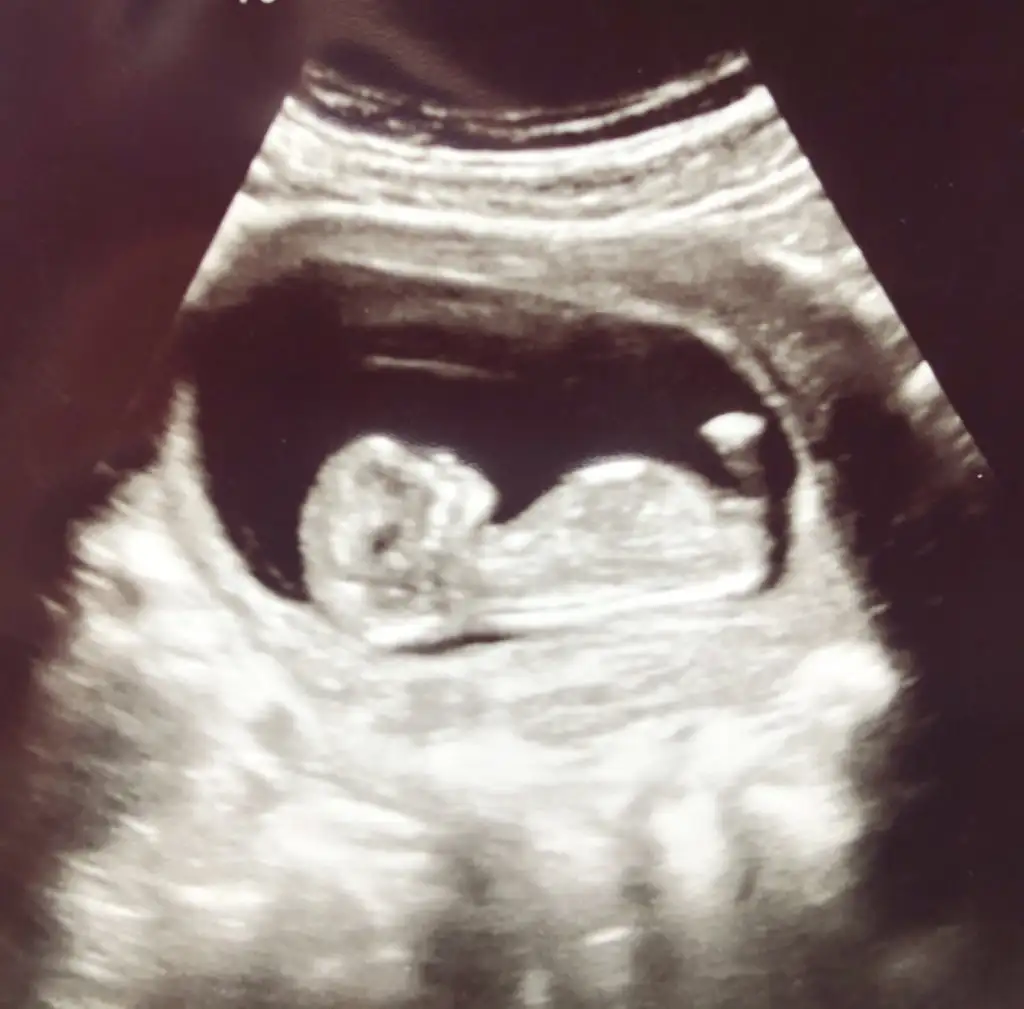

Kızlar yorum alabilir miyim

Eklentiler

• 2155548D-75AE-4972-9499-B9D4ED09C62B.webp

8,8 KB · Görüntüleme: 70

Slm canlarım bi arkadaşımın 13.haftada yorum yapabilir misiniz